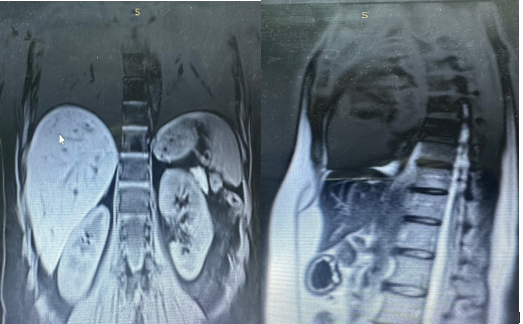

In March 2024, FDG PET/CT showed no residual active metabolic damage and a favorable response to oncological treatment (Figure 8).

Figure 8: PET/CT showing no residual active metabolic damage

In june 2024, an abdominal MRI was performed, without notable particularities in the oncological context (Figure 9).

Figure 9: Abdominal MRI